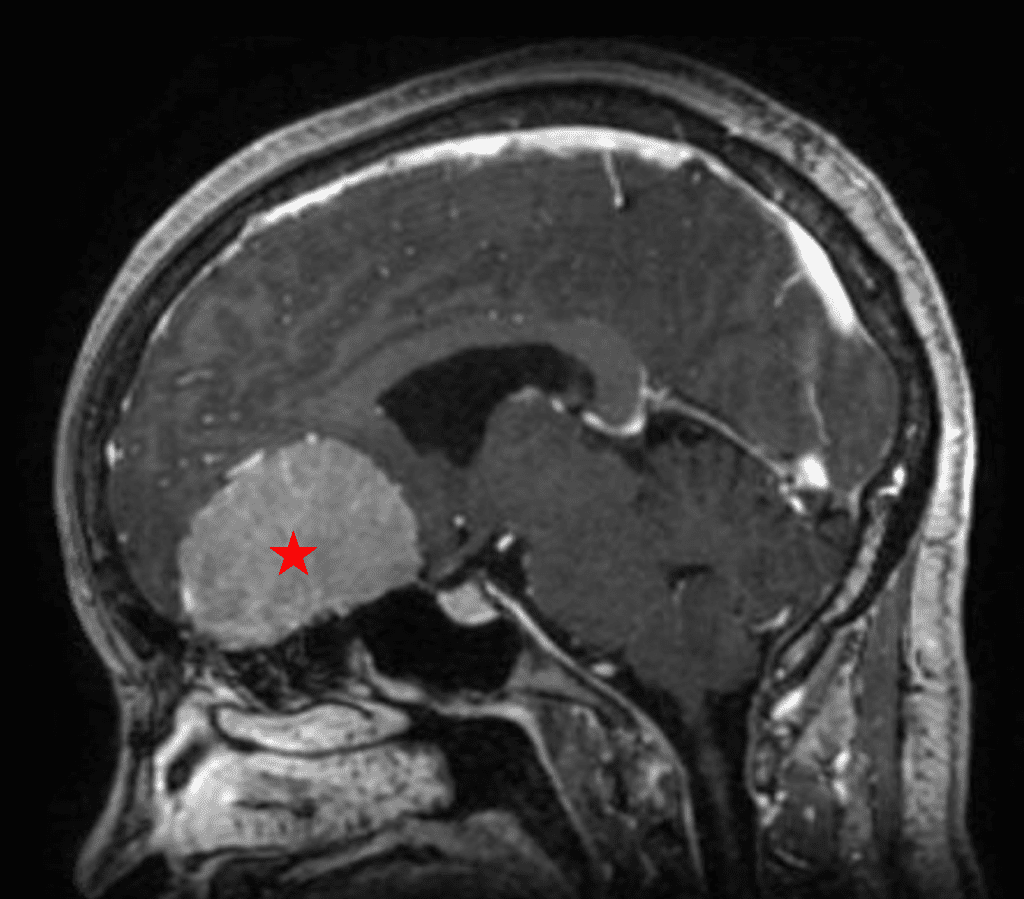

Figure 2a – Preoperative MRI demonstrating an extra-axial lesion with surrounding vasogenic edema and mass effect on the frontal lobes.

Figure 2b – Postoperative MRI demonstrating resolution of mass effect.

She was started on high-dose steroid and antiseizure prophylactic medicine. Surgical intervention was offered for mass effect, symptomatic relief, neurologic preservation, and histopathologic diagnosis. Dr. Gaudin performed a bifrontal craniotomy with complete resection of neoplasm through an interhemispheric and subfrontal approach. Postoperative imaging demonstrated a gross total resection without residual tumor and resolution of mass effect (Figure 1b and 2b). Intraoperative pathology was consistent with meningioma, WHO grade 1. She recovered very well, and was discharged home on postoperative day 3. On her follow-up outpatient visit, her preoperative symptoms had fully resolved, and her olfactory sense was maintained.